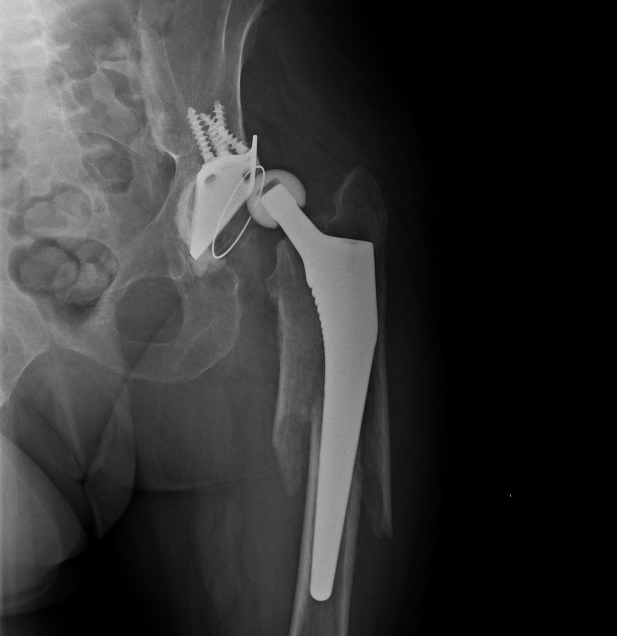

Надежность, если все правильно сделано, как минимум достаточная для

любых нагрузок. Не понял насчет "был бы тех же размеров" - это и есть

оскольчатый перелом, вот снимок до операции. Никаких верхних доступов,

все закрыто. Принципы АО - вещь переменная, в конце 2013 г. издана

аошная книжка про перипротезные переломы, там уже есть про эту методику.